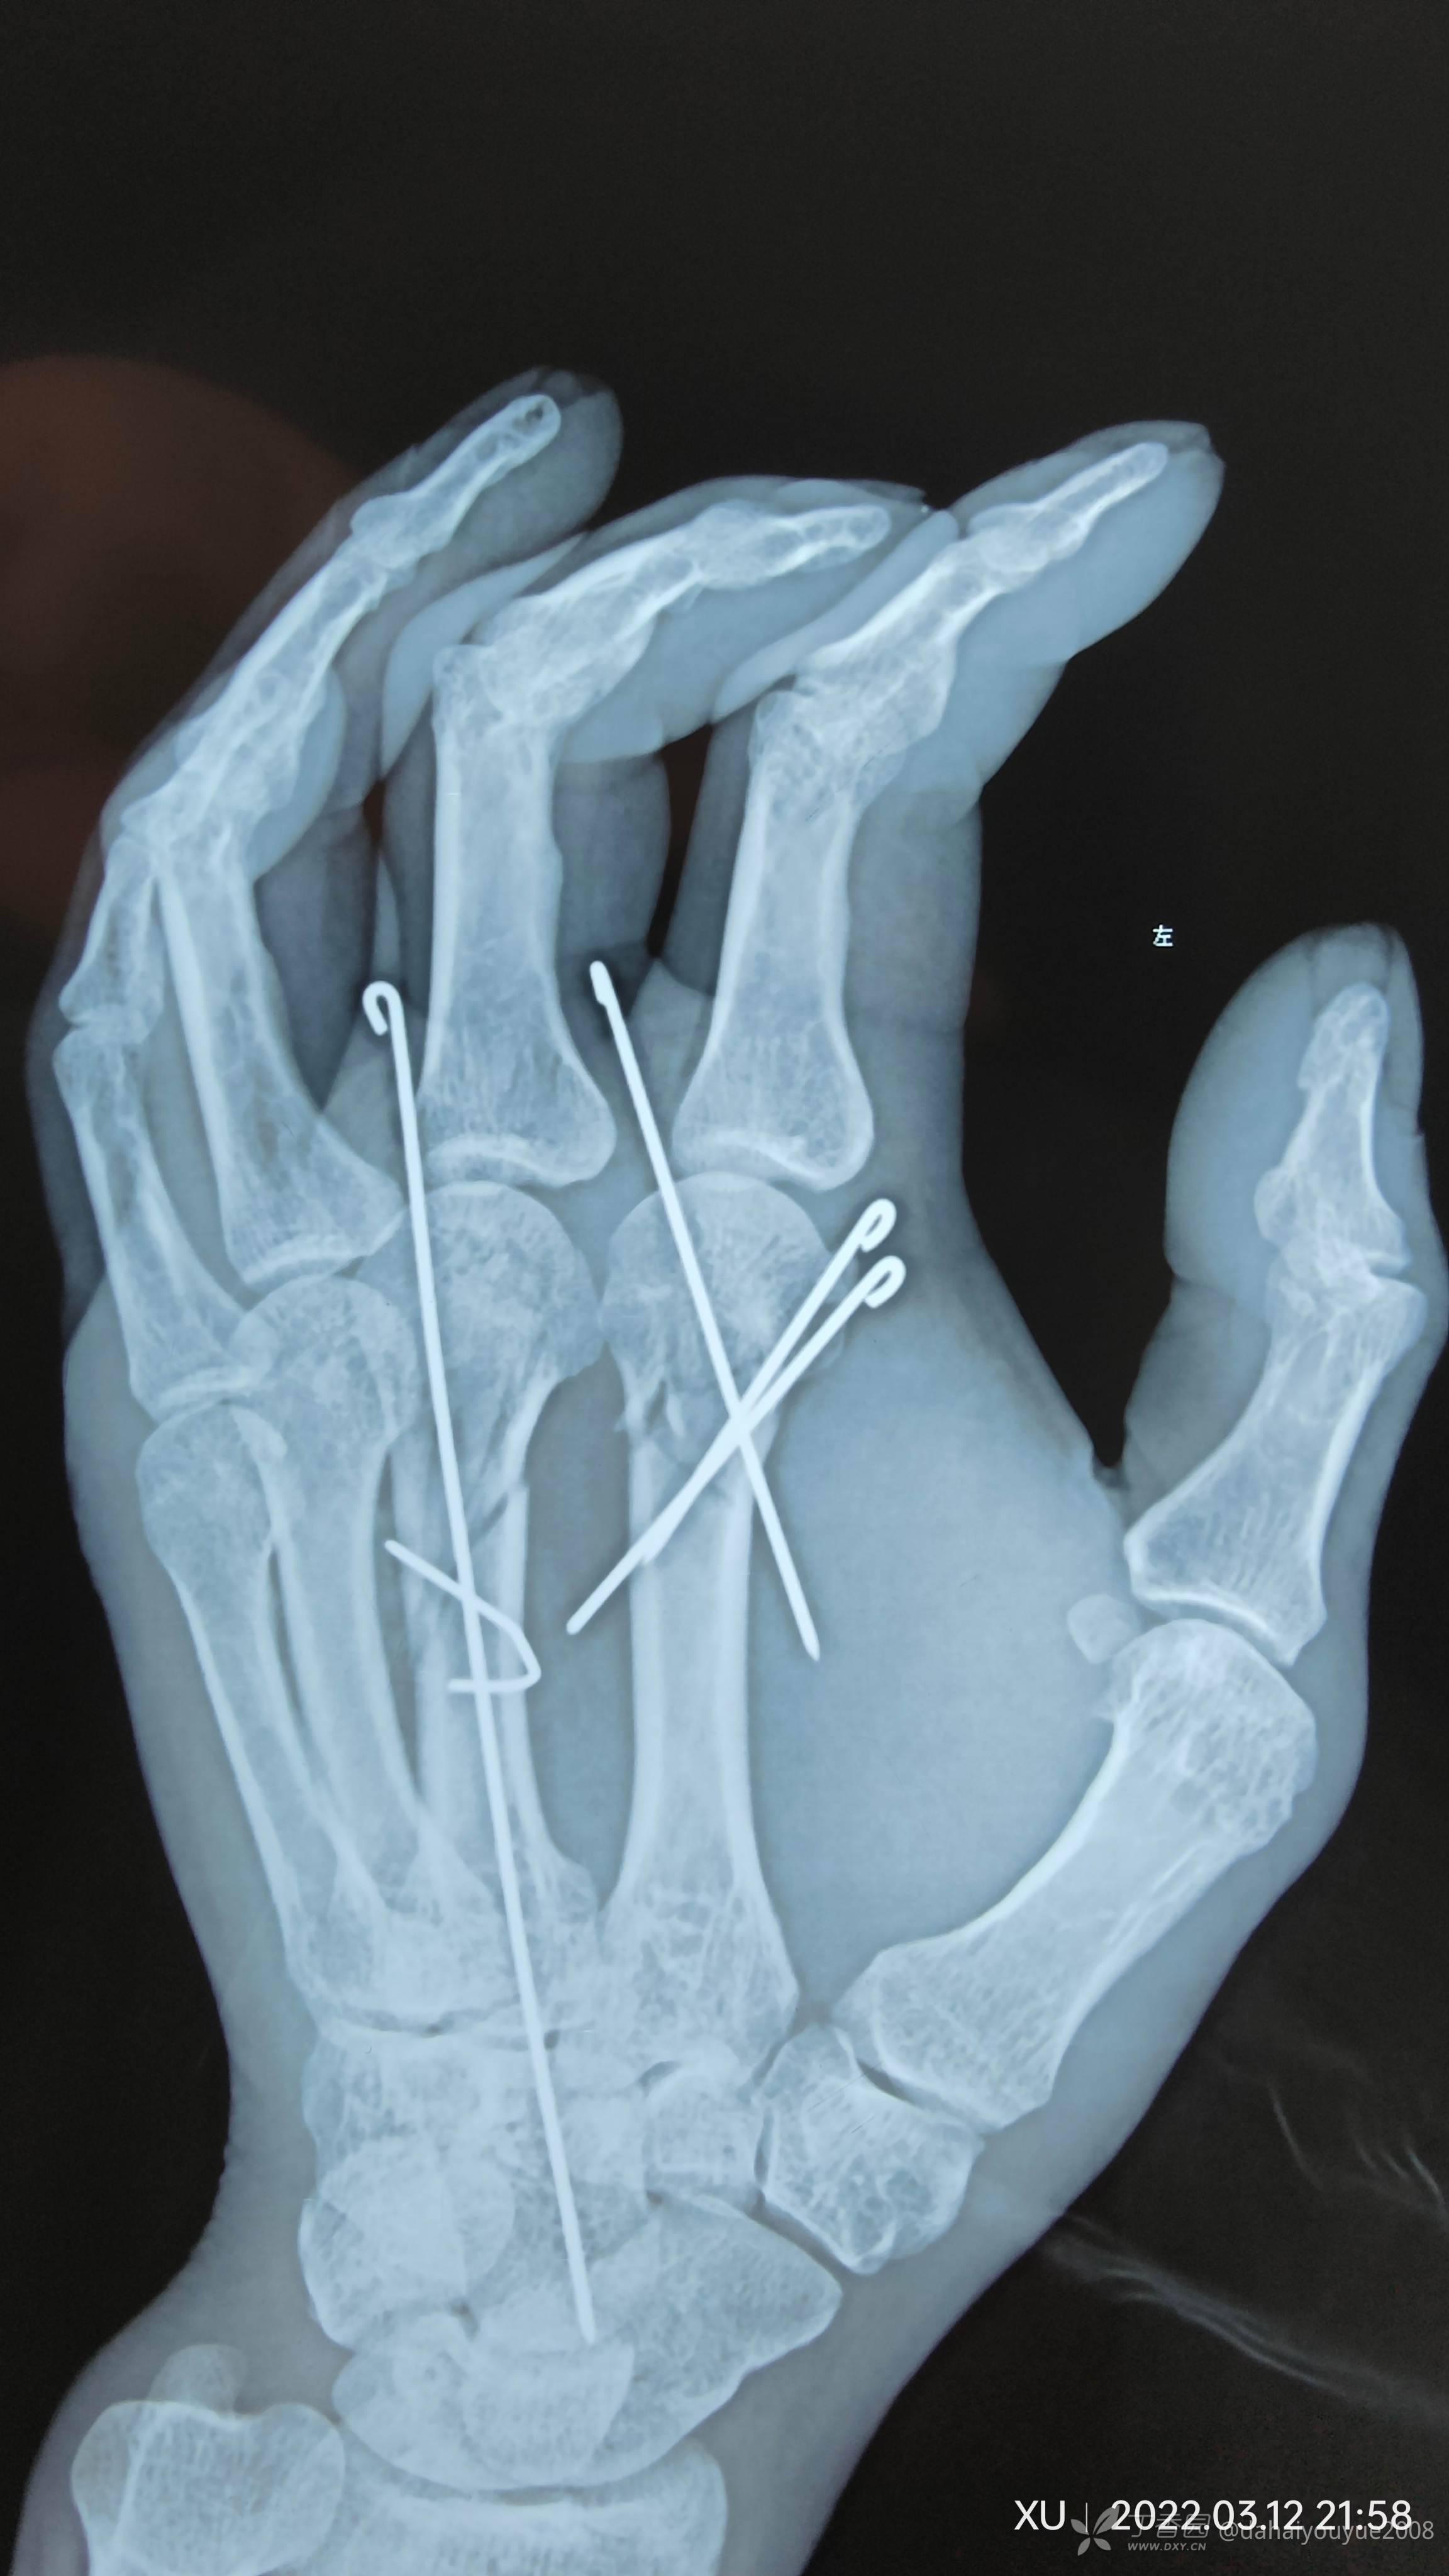

二,掌骨粉碎性骨折捆绑(术中未拍照片,术后效果还不错)